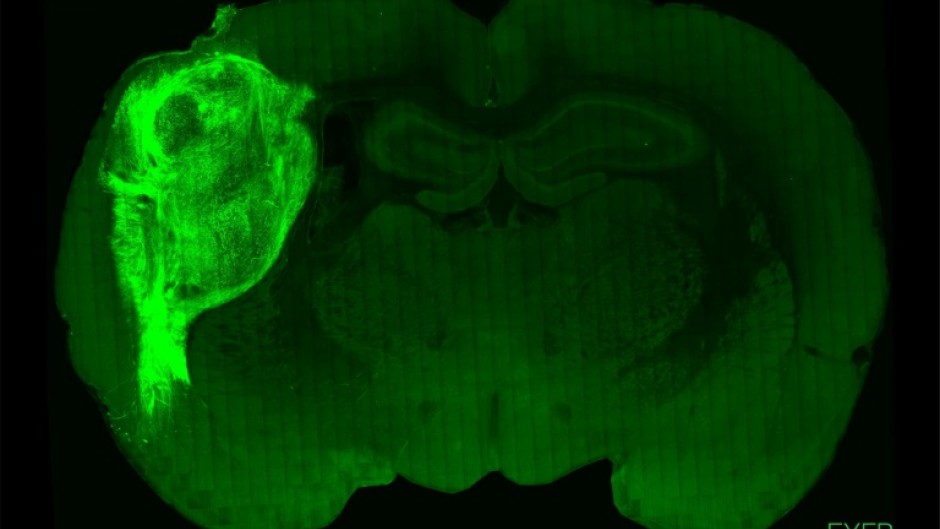

To overcome those limitations, researchers implanted the groupings of human brain cells, called organoids, into the brains of young rats.

"By transplanting them at these early stages, we found that these organoids can grow relatively large, they become vascularised (receive nutrients) by the rat, and they can cover about a third of a rat's (brain) hemisphere," Pasca said.